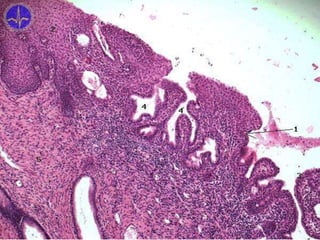

Ovary – internal structure

• superficial (Müllerian) epithelium – simple

cuboidal with microvilli

– original coelomic epithelium (mesothelium

ovaricum)

– borderline with mesothelium = linea of Farre-

Waldeyer

• tunica albuginea

• stroma ovarii

• connective tissue (collagen and reticular fibers, fibroblasts)

– cortex – folliculi ovarici

• corpus luteum, rubrum, albicans

– medulla

Follicle stages

• primordial follicle

• primary follicle

• secondary follicle

• tertiary follicle

• matured Graafian

follicle

• just below the ovarian surface

• one layer of flattened follicular cells

(epitheliocyti folliculares; folliculocyti primordiales)

= simple squamous epithelium (epithelium

simplex squamosum)

• oocytus primarius

– large eccentric nucleus and

nucleolus

– yolk nucleus (Golgi apparatus,

mitochondria, inclusions, centrioles)

Folliculi ovarici primordiales

Primordial follicles

Folliculi ovarici primarii

Primary follicles

• follicular cells proliferate → simple cuboidal to

columnar epithelium (epithelium simplex

cuboideum)

– increase of lipid granules → granulosa cells

• zona pellucida

– between cells and oocyte (glycoproteins

produced by both populations)

• epithelium stratificatum cuboideum

• prominent basal lamina and zona pellucida

• theca folliculi (follicular sheath)

– thickening of adjacent connective tissue and

stromal cells